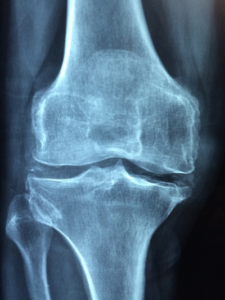

- اختبار كثافة العظام.

اختبار كثافة العظام

فحص كثافة العظام أحد أهم الفحوص في تحليل الهشاشة للسيدات، كذلك كونه إجراءً سريعًا وغير مؤلم.

يتضمن الاستلقاء على الظهر على طاولة الأشعة السينية (DEXA)، كذلك يمكن البقاء بالملابس كاملة عدا منطقة الفحص، ونزيل أي ملابس بها قطع أو أجزاء معدنية.

يقارَن فحص كثافة العظام مع كثافة العظام المتوقعة لشاب بالغ يتمتع بصحة جيدة.

نحسب الفرق على أنه درجة الانحراف المعياري (SD)، ويقيس الفرق بين كثافة عظام المريض والقيمة المتوقعة.

يُعرف الفرق بين قياس كثافة عظام المريض وقياس الشاب البالغ الأصحاء بدرجة T.

تُصنف منظمة الصحة العالمية (WHO) درجة T على النحو التالي:

- نعده أمرًا طبيعيًا عندما تكون T فوق -1 SD.

- يُعرف أنه انخفاض طفيف في كثافة المعادن في العظام (BMD)، عندما تُصبح T بين -1 و-2.5 SD.

- يُعرف بأنه هشاشة العظام، عندما تكون T عند أو أقل من -2.5 SD.

على الرغم من أن نتائج كثافة العظام توفر مؤشرًا جيدًا على قوة العظام، إلا إنها لن تتنبأ بما إذا كان الشخص سيصاب بكسر أم لا.

هذا لأن عوامل أخرى، مثل العمر أو الجنس أو ما إذا تعرض الشخص للسقوط سابقًا، تحدد أيضًا ما إذا كان سيُصاب بكسر.